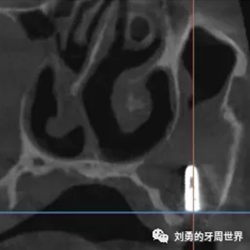

在手術(shù)之前行ct檢查如下圖:

可見B5種植體已經(jīng)脫落進(jìn)入上頜竇,而上頜竇黏膜已經(jīng)出現(xiàn)明顯的炎癥,上頜竇黏膜明顯增厚,(在二期切開手術(shù)之前上頜竇黏膜厚度正常)。而在ct上可以看到左側(cè)上頜竇中鼻道開口不通暢。